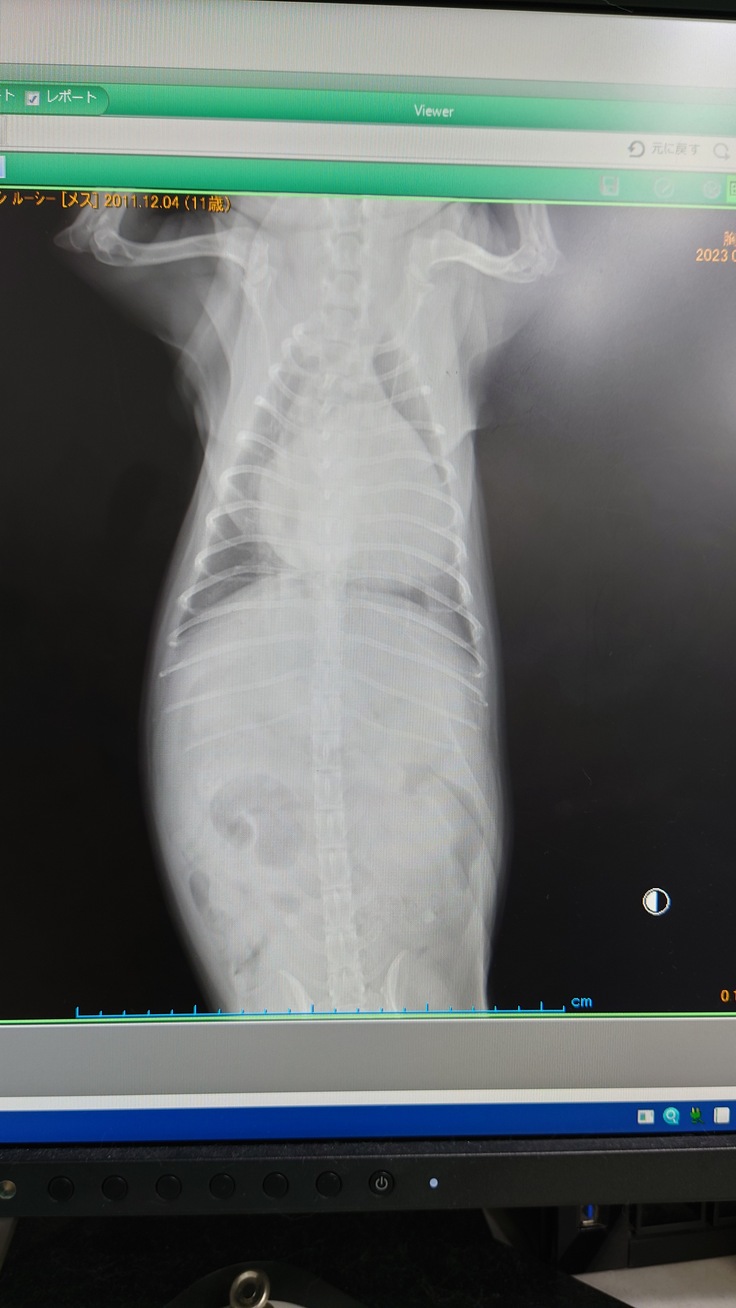

すぐにレントゲンを撮って肺の状態を確認しました。

五日前のレントゲンよりも肺の水の量が増してしまっていたようで

呼吸が荒くなっていたようです。

ギリギリ肺水腫にならなかった、状態とのことだそうです。